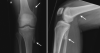

Fibrodysplasia ossificans progressiva (FOP) is a rare genetic disorder and the most disabling condition of heterotopic (extraskeletal) ossification in humans. Extraskeletal bone formation associated with inflammation preceding the osseous conversion usually begins in the first decade, predominantly in the head, neck, and shoulders. All patients have malformed great toes. Most patients have a spontaneous mutation of the ACVR1 gene. We report a 17-year-old girl with malformed great toes who had her first episode of heterotopic ossification and impaired mobility of the left hip at the age of 13 years. No inflammatory fibroproliferative masses preceded the onset of heterotopic ossification. Radiographic studies demonstrated myositis ossificans, but failure to associate the great toe malformation with heterotopic ossification led to a failure to diagnose FOP. She underwent repeated and unnecessary operative procedures to remove a recurrent lesion. FOP was finally suspected when the great toe malformation was correlated with the trauma-induced heterotopic ossification. Genetic analysis confirmed the presence of the classic FOP mutation (ACVR1 c.617G>A; R206H). This case highlights the importance of examining the great toes in anyone with heterotopic ossification. The association of malformations of the great toe with heterotopic ossification in all cases of classic FOP will lead to prompt clinical diagnosis and the prevention of iatrogenic harm.